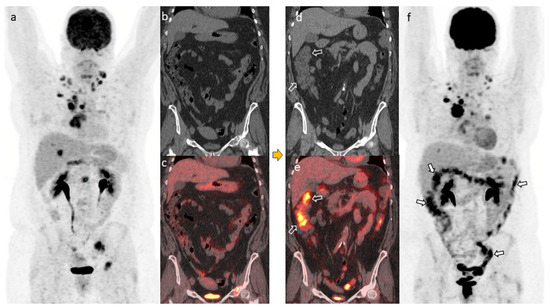

4.1. Case #1